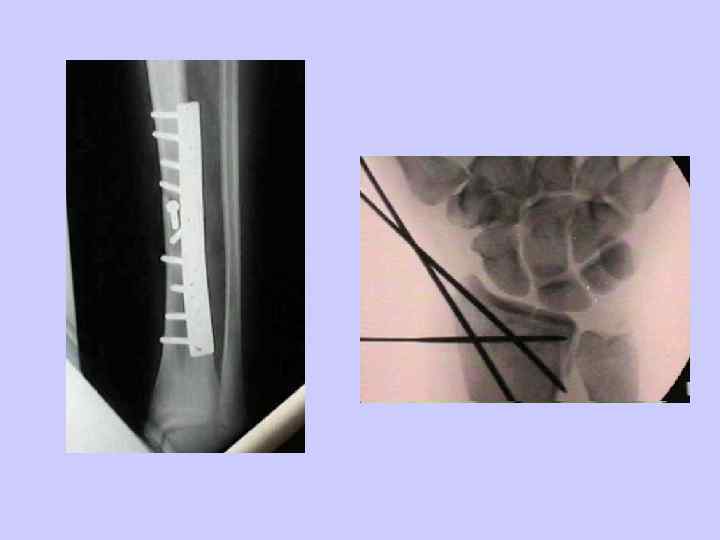

Как удержать репозицию • Гипс? • Внутренняя фиксация (накостно/внутрикостно • Наружная фиксация (чрезкостно)

Внутренняя фиксация • Пластины и винты • спицы (Kirschner) • Внутрикостные стержни